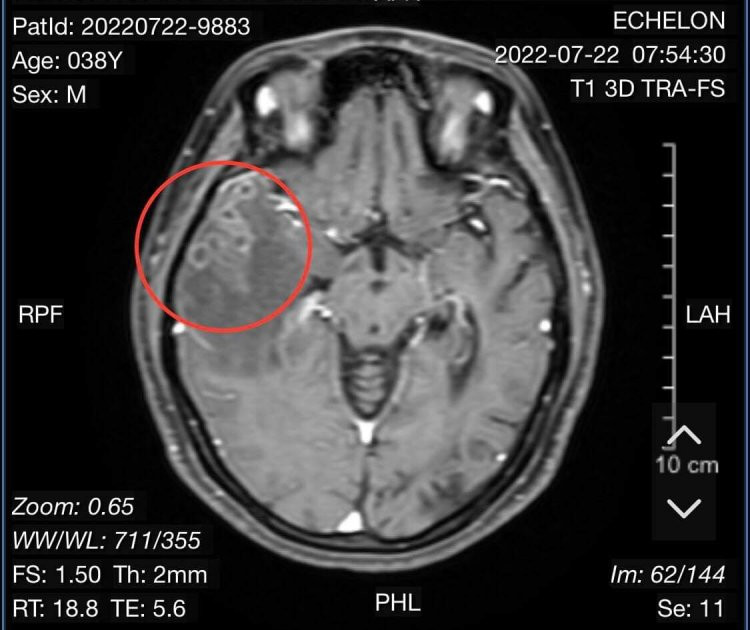

Vào Bệnh viện Hữu nghị Việt Nam - Cuba Đồng Hới, qua hình ảnh chụp cổng hưởng từ sọ não cho thấy người bệnh bị tổn thương não do sán. Kết quả xét nghiệm giải phẫu bệnh là mô não có nhiều ổ viêm hạt, trung tâm chất hoại tử, bao quanh lympho...